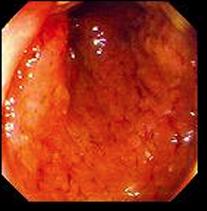

Stade precoce : Lesion

congestif ( oedemateuse ) |